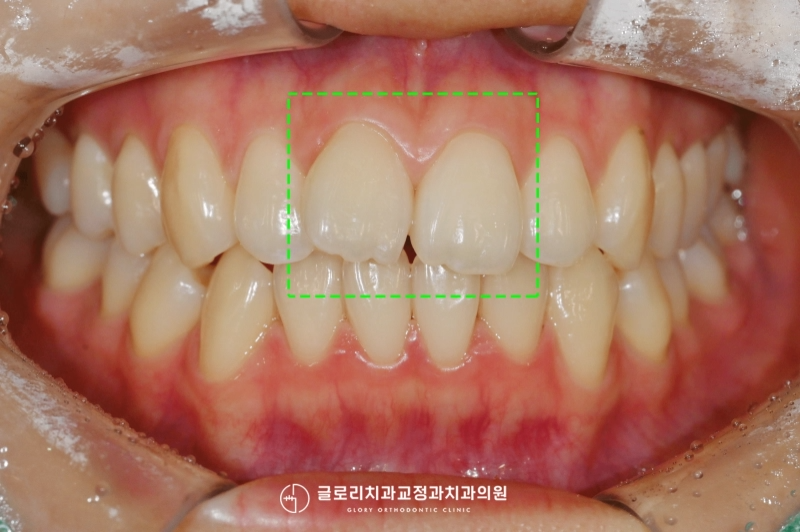

3. 완료

치료 기간은 4개월이 소요되었습니다.

생각보다 빠르게 완료가 되었죠^^

완료된 사진을 보시면

처음의 문제들이 잘 해결되었는데요.

틀어져 보였던 전치부가

이제는 가지런히 정렬이 되었고,

보기에도 더 예뻐진 느낌이 듭니다.